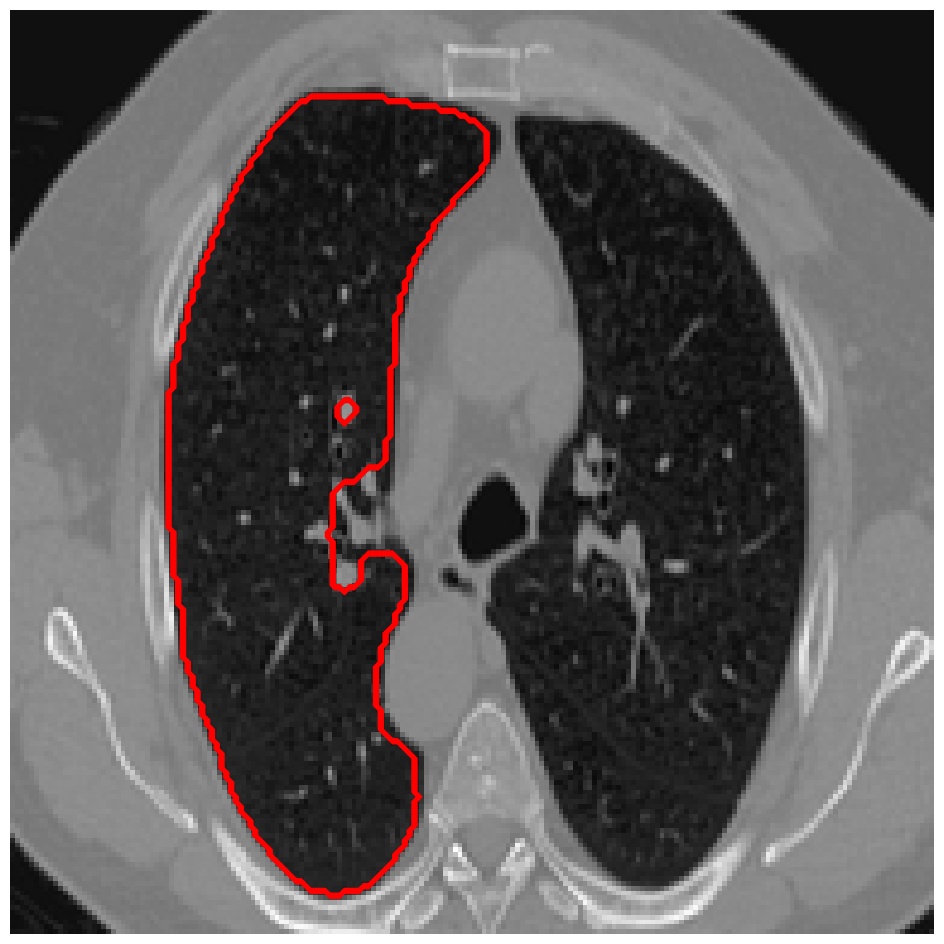

Figure 4: A sample result on the Lung data. We display the input image with the user input \mathcal{M}, the ground truth (GT) and results from the four methods. Moreover, we show comparisons with the model (4) solved in a variational framework with both Total Variation (TV) and Euler Elastica as explicit regularisation, as well as a comparison with the model solved in a Deep Image Prior framework.

In Figures 3 and 4 we show two select images from the test set for the Lung images to qualitatively show some results. To begin, we show some results of the model (1) solved with a Total Variation (TV) [21] regulariser, and with a Euler Elastica [22] regulariser. In addition, we show a result with the model (1) in a typical Deep Image Prior framework (i.e. training a network specifically for that image without the explicit regularisation in the loss function, employing early stopping). We see that the result from M4 is an improvement over the TV and Elastica models, whereas results from the DIP example is comparable. However, the DIP example requires a new network trained specifically for the new image, whereas our result is acquired after training. In addition to the explicit regularisation comparison, we also display the results from the four methods (all of which are trained previously on 222 images and used for prediction). Moreover some quantitative results are shown in table 1, which shows the mean DICE score and standard deviation on the 16 images in the test set.